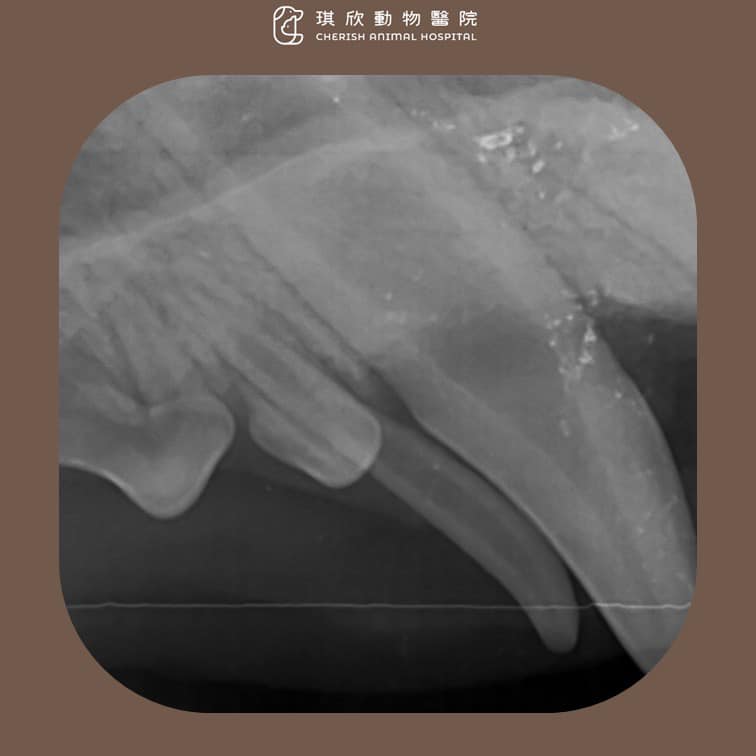

這是一隻小型犬,因為乳牙沒有自行脫落,導致恆齒被迫從異常角度萌出。X 光檢查顯示乳牙與恆齒位置重疊,若不及時處理,將持續造成牙齦發炎及牙齒擁擠。

X 光檢查:確認牙根與恆齒位置。